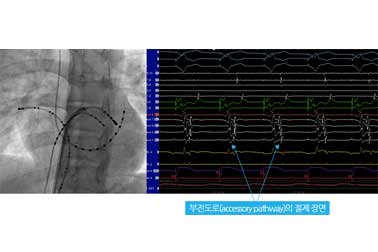

- 부정맥의 여러종류 가운데 약물 치료가 효과적이지 못하고, 근본적 치료가 어려운 경우 전극도자 절제술을 이용하여 치료합니다.

- 심장내에 여러 전극도자를 설치하고, 부정맥 발생 위치를 확인하고 전기적 에너지를 이용하여 심장 내 조직을 괴사시켜 치료를 합니다.

- 소아 환자에서는 주로 상심실성 빈맥, 심방 빈맥, 심실 빈맥 등의 환자에 시술이 이루어 지고 있습니다.

심장내 전극도자

심장내 심전도

방실 회귀성 빈맥환자에서의 전극도자 절제술